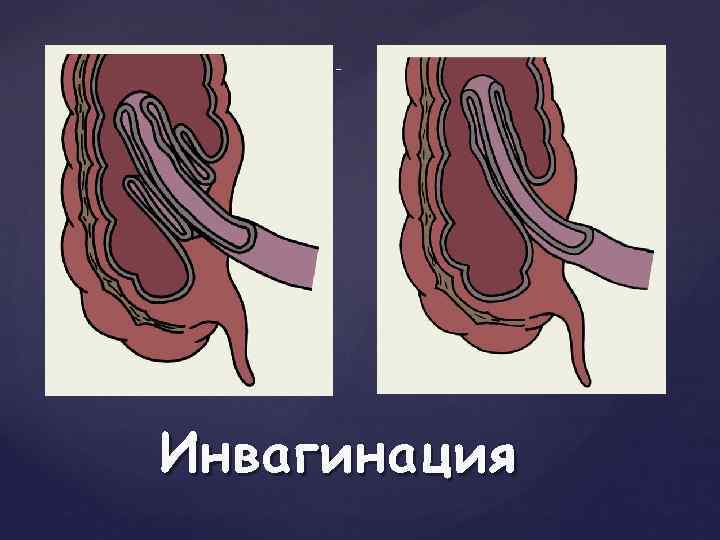

Странгуляцияға ішек бұралуы, байлануы, қысылуы, күрмелуі себеп болады. Обтурациялық түрінде ішек ісікпен, аскаридамен, дәкелі құрғатқыш (операцияда ұмытылған) бітеледі. Қан айналысы онша бұзылмайды. Өйткені шажырқай қысылмайды. Ішек түйілуінің келесі себебі инвагинация - ішекке ішек еніп оның бітелуіне қоса шажырқайдың қысылып, қан айналысы бұзылуы байқалатындығынан илеустің бұл түрінде обтурация және странгуляция қоса байқалады. Ішектің қабырғасының тегіс етінің әлсізденуіне байланысты кездесетін ішек түйілуі динамикалық деп аталады. Илеустің бұл түрін тырысқан және салды деп екіге бөледі. Спастикалық түрі - ішек қабырғасының тырысуынан оның өзегі тарылуымен байланысты болса, паралитикалық илеусте ішек созылған, өзегі кеңіген, оның тонусы - қозғалуы нашарланған.

{ Схематическое изображение инвагинации тонкой кишки в слепую — двойная инвагинация { Схематическое изображение инвагинации тонкой кишки в слепую — одиночная инвагинация Инвагинация

. Ащы ішектің (заворот) айналуы . Ішектің ішекке енуі – (инвагинация).